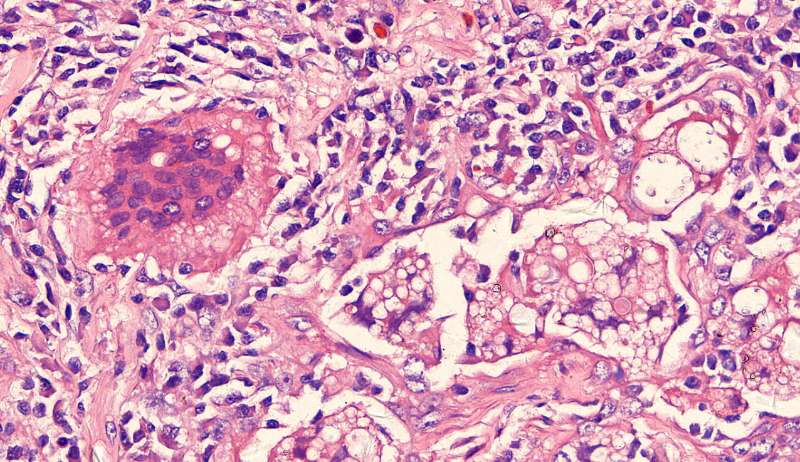

隐球菌

结节状,周围型,宽基底,巨噬细胞多而且大,有纤维组织,所以经常有点收缩力

这些就是隐球菌,常被巨噬细胞吞噬,大多为多核巨噬细胞 隐球菌感染,在免疫力正常情况下,就是个肉芽肿 小白球,略显淡蓝色,这是荚膜的感觉

隐球菌在HE染色是小白球,隐隐的,球状的。在PAS染色是红色的小球,在六铵银染色是黑褐色的小球。

王:谁能说说这两幅?

戴畅:有散在的隐球菌及中性粒细胞 吕海容:有一些小泡泡是隐球菌,有纤维,有炎性细胞。

红圈是多核巨噬细胞,与结核有点区别,结核的langhans细胞核排列成大半圈,马蹄形

这里红色束状的是纤维,有胶原